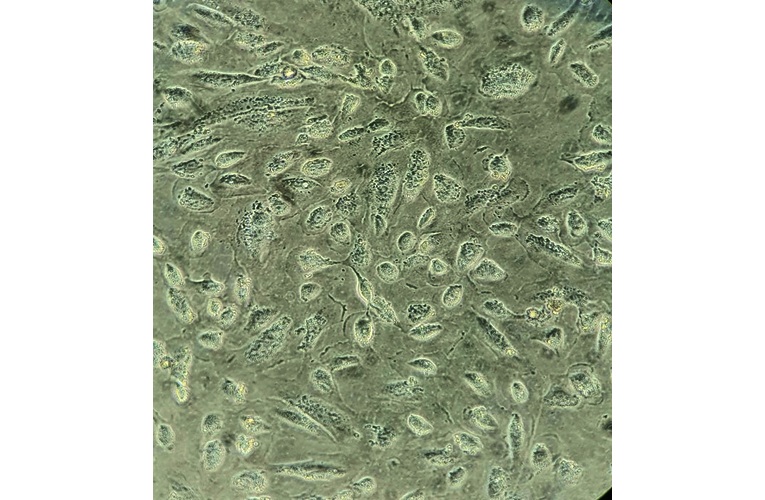

- Morphology: Predominant epithelial appearance with slight spindle like elongated mesenchymal features

- Growth properties: Adherent

- Description: The cell line established directly from a tumor compartment (primary tumor) of chemonaive HGSOC patient. Thus it closely recapitulates the tumor compartment as it emerged in these patients.

- Subculture routine: Very slow growing cell line (doubeling time is roughly 2 weeks). Trypsinize for 3-4 minutes in 37C until cells separate, add growth media (X4 volumes of trypsin). Split 1:2. Resuspend in growth media